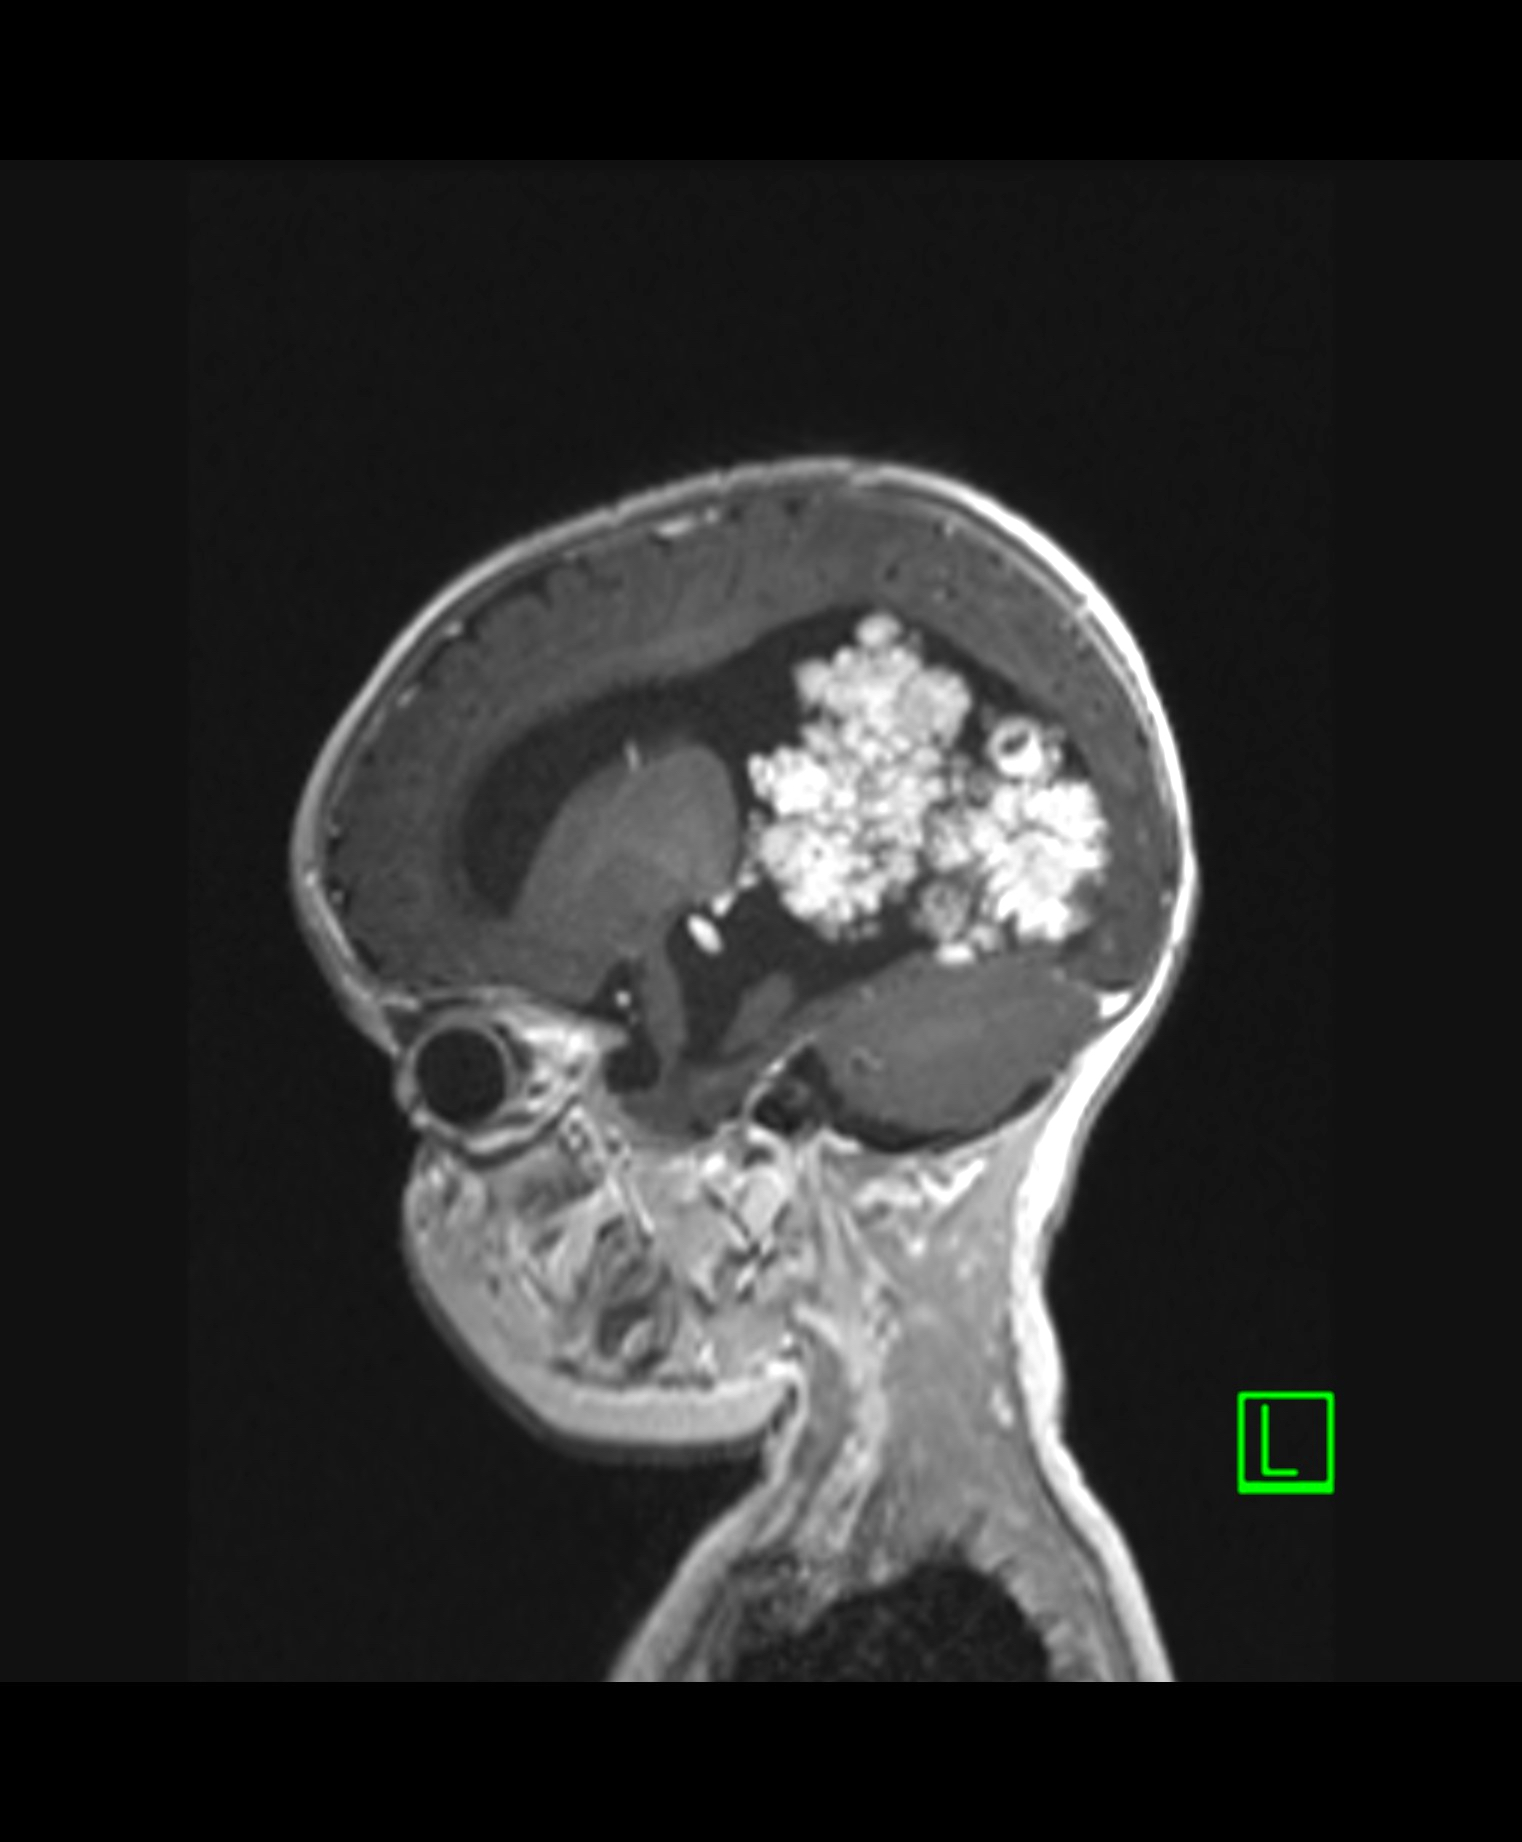

Radiology description

- Intraventricular papillary or lobulated lesions on MRI; hypo or isointense on T1, hyper or isointense on T2 and enhanced in postcontrast imaging (Cancer Imaging 2019;19:17)